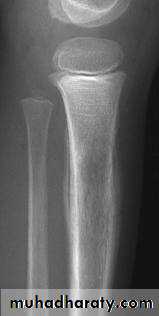

show a radiolucent area situated eccentrically at the end of a long bone and bounded by the sub- chondral bone plate.

The endosteal margin may be quite obvious, but in aggressive lesions it is ill-defined.

X-rays42

The Centre sometimes has a soap-bubble appearance.

The cortex is thin and sometimes ballooned. aggressive lesions extend into the soft tissue.43

The appearance of a ‘cystic’ lesion in mature bone, extending right up to the subchondral plate, is so characteristic